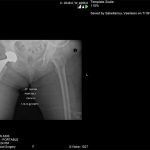

Ο ορθοπεδικός – χειρούργος Βασίλειος Σακελλαρίου στην Αθήνα αντιμετωπίζει επιτυχώς κάθε είδους κακώσεις γόνατος και ισχίου. Παρακάτω παρουσιάζονται πολλές περιπτώσεις κακώσεων που αντιμετωπίστηκαν επιτυχώς από τον χειρούργο – ορθοπεδικό. Δείτε τις αναλυτικά: